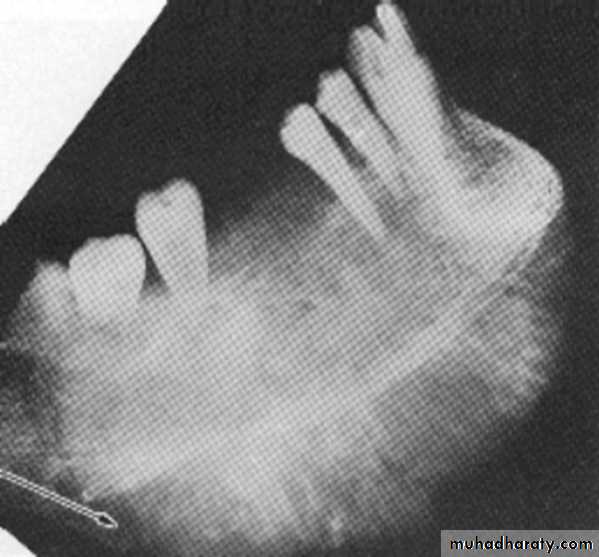

Location: posterior body of the mandible.

Periphery: ill defined with gradual transition to normal trabeculae.

Internal structure: *Decrease in bone density.

* Loss of trabecular sharpness.

*Scattered areas of radiolucency.

* Sclerotic regions → sequestra.

Effect on surrounding structures:

*Bone resorption or bone formation.*Bone formation is parallel to bone surface and lift the periosteum.

*A radiolucent band separates this periosteal new

bone from the bone surface.

This is continue to form several radiopaque lines

separated by radiolucent bands (Onion-skin

appearance) → Proliferative periostitis